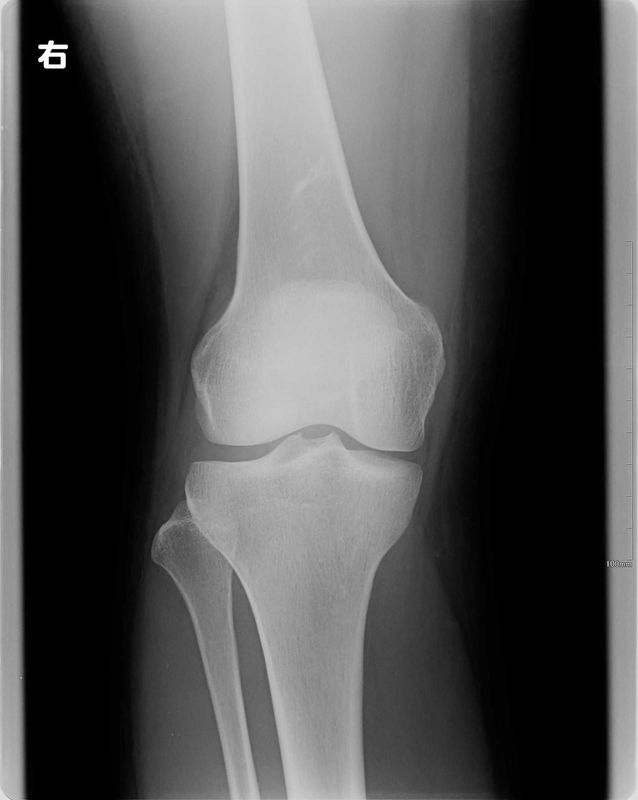

レントゲン所見

| 手術前 | 手術後 |

![]() |

| 骨傷・変形はない | 異常なし |